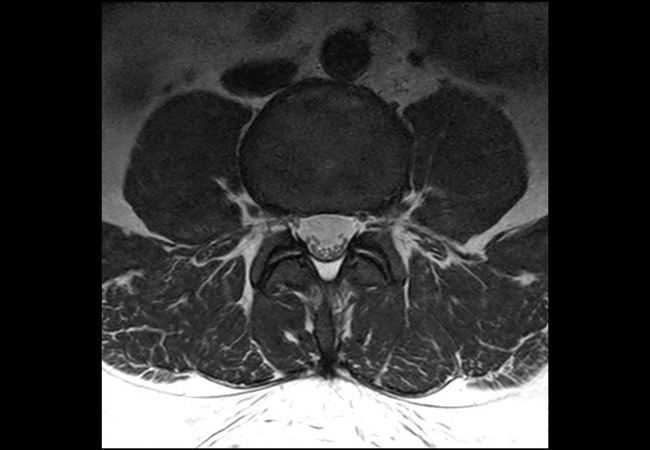

This is a lumbar spine examination of a young obese patient (170 kg) with right sciatic pain. The main difference in the protocol for this obese patient is that the voxel size is around 15-20% larger than in our standard protocol. This patient's weight will vastly increase the minimum TR requirements under the SAR modelling of any 3T scanner. The larger voxel helps both in reducing this increase in scan time and reduces SAR.The MultiTransmit technology evens out the flip angle and SAR across these large fields of view, even when filled with such a large patient, and the dStream coils and SmartSelect technology allows maximum penetration to allow for excellent SNR.The images demonstrate the high SNR provided by dStream and achieved with SmartSelect, which uses a quantitative method to determine and activate all coils that increase SNR. Imaging penetrated 150 mm of fat to reach this patient’s lower L-spine.

Axial T2w TSE